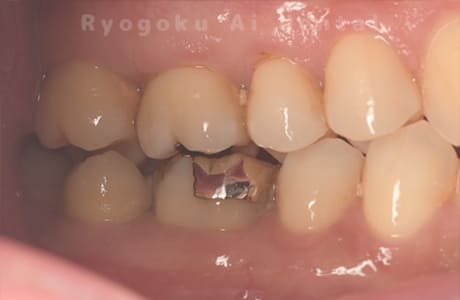

Case12

-

- 原因

- 歯牙破折

- 治療内容

- 自家歯牙移植

- 治療費用

- 220,000円

右上の違和感が取れず、ご来院された患者様です。歯が割れており、抜歯を行い、反対側の親知らずを移植しました。

<リスク・副作用>

治療後、痛みや違和感、出血、腫れなどが出る事があります。喫煙者、糖尿病などの方の場合、歯が生着しない場合があります。